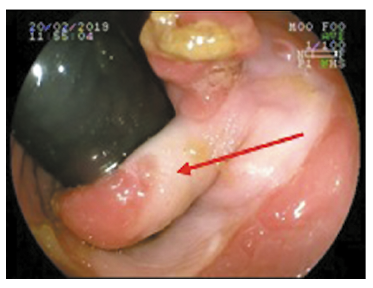

Al tacto rectal, se palpa puente transversal a nivel de recto bajo próximo al canal anal, de consistencia fibro-elástica, que divide la luz en dos hemicircunferencias. La mucosa rectal presentaba lesiones polipoideas blandas y móviles.

Se realizó videocolonoscopía, observándose a nivel de recto bajo próximo a canal anal puente mucoso de 10 mm de grosor que dificultaba el pasaje del endoscopio (Figuras 1 y 2).